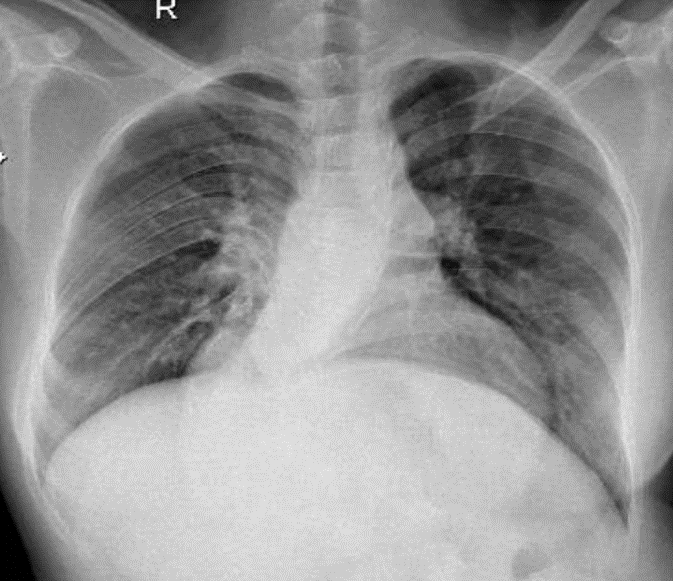

Hãy phân tích tình huống Nữ 29 tuổi -CĐ: Thông liên thất, tang áp phổi nặng, hội chứng eissenmenger

1-Tăng tuần hoàn hai phổi